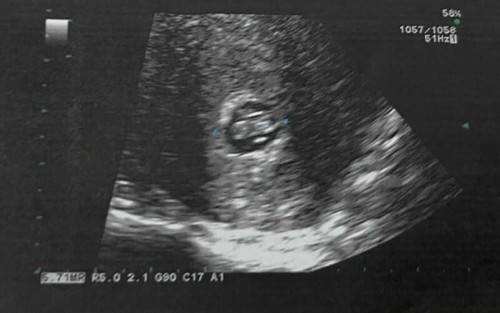

ตั้งครรภ์ 7 สัปดาห์ 4 วัน มีอาการปวดท้องน้อยเหมือนปวดประจำเดือน (ปวดมาก) และมีเลือดซึมออกตลอดทั้งวัน หมอวินิจฉัยว่ามีภาวะแท้งคุกคาม ทำการ U/S แล้วพบว่าน้องยังหัวใจเต้นอยู่ มีโอกาสตั้งครรภ์ต่อไปได้ 50/50 คุณหมอฉีดยากันแท้งและจ่ายยาฮอร์โมนให้กลับมากิน #แบบนี้มีหวังไหมคะ มีคุณแม่ท่านใดบ้างที่มีภาวะแบบนี้แล้วสามารถตั้งครรภ์ต่อไปได้จนคลอดน้องออกมาสมบูรณ์แข็งแรง รบกวนขอคำแนะนำด้วยค่ะ ตอนนี้เรากังวลใจมากเลย 😭 #ท้องแรกค่ะ #ขอบคุณล่วงหน้านะคะ